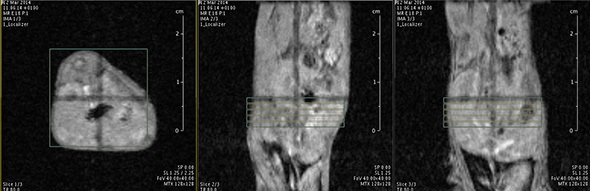

MRI is based on NMR Spectroscopy, which is the best language to talk to nature. We know how it is important to exploit different field strengths in order to extract maximum information from the system that we are investigating.

I think that also the low-field, let’s say the low/intermediate field to work at the 1 Tesla for instance as in the case of this beautiful Icon system, this gave us unique possibilities. Anytime we use a gadolinium-based agent or more in general a paramagnetic basic agent the best field is the 1 Tesla.

So, we can show that there is a real advantage of working at 1 Tesla in comparison to for instance 7 or 9 Tesla when one is using a relaxation enhancer to target a specific epitope in the region of interest.